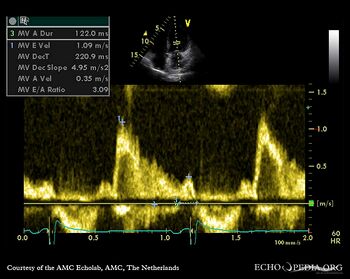

Diastloic dysfunction (pseudonormalisation)

A3CH Pulsed-wave Doppler signal of mitral inflow: E>A